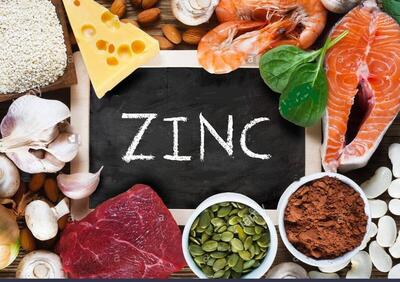

درمان سریع گلودرد با 9 روش خانگی!!

درمان سریع گلودرد: داروهای زیادی برای درمان عفونت گلو در بازار وجود دارند. اما یکی از بهترین مواردی که میتوان با آن به پاکسازی گلو و ریه پرداخت، روتارین است.